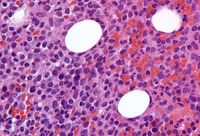

Cytospin prepared from bone marrow aspirate illustrates the typical cell cytology, with oval- to bean-shaped nuclei and moderate amounts of cytoplasm with irregular cytoplasmic borders (Wright Giemsa 100x oil)

From the collection of Lynn Moscinski, MD; used with permission